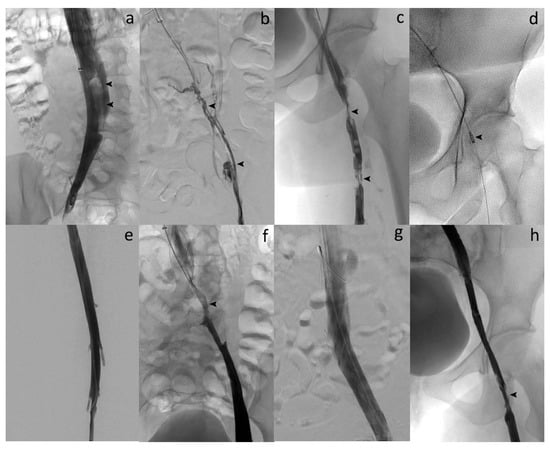

The popliteal approach was preferred in most of patients (73.3%) (Figure 1). A temporary retrieval ALN IVC filter was used in 11 (36.7%) of the 30 patients and removed between 1 and 2 months after the procedure. The technical success rate was 100%. No lytic therapy infusion through any catheter left in place was needed. The stenting rate was 100%. No major complications, such as bleeding or additional pulmonary embolism, occurred. No blood transfusion was needed. Two minor complications were reported: a broken and lost wire that was snared in 1 patient; and a broken device helix outside the patient. No device-related complications occurred. Treatment duration ranged from 70 to 180 min. In 5 of the cases, a 10 mg tissue-plasminogen activator (t-PA) bolus injection was performed into the occluded venous segment to complete the procedure, only as an adjunctive medication, at the discretion of the interventional radiologist. No catheter-directed thrombolysis (CDT) with catheter infusion was needed. A mean of 2.3 dedicated venous stents were implanted per patient. Procedural details and safety data are given in Table 2 and Table 3.

Figure 1. Acute symptomatic ilio-femoral LET III DVT in a 35-year-old woman. (a) Left lower extremity venogram in prone position by popliteal approach shows patent femoral vein (arrow). (b) Venography reveals no flow within the left common femoral vein (arrow). (c) Phlebography confirms complete thrombosis of the left iliofemoral vein (arrows). (d) Enlargement of the thrombosed common left iliac vein segment (arrow). (e) Venography after percutaneous mechanical thrombectomy (PMT) with the 10-French Aspirex®S device shows flow restoration but narrowing at the common femoral vein level (arrow). (f) Opacification shows outflow obstruction at the common iliac vein level, too (arrow). (g) Stent placement at both venous levels with balloon dilation (arrows). (h) Final venography after stent placement reveals successful recanalized common iliac/femoral flow with disappearance of symptoms within 2 days and no recurrence.